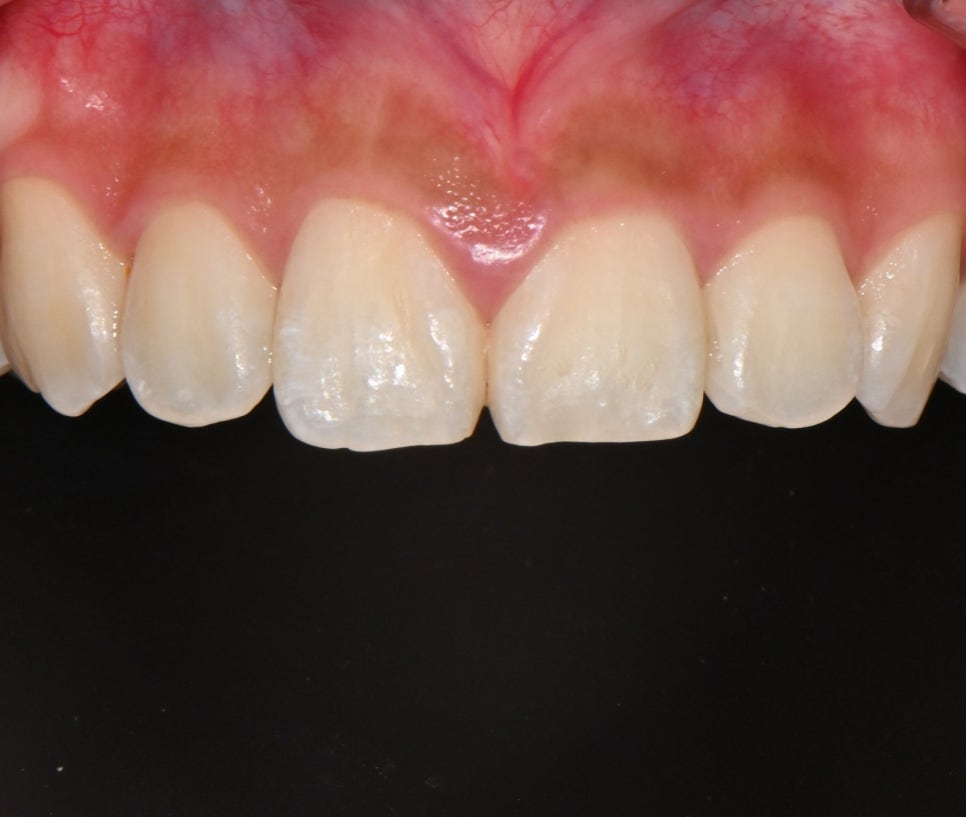

📸 Before

– Dark tooth tone

– Slightly asymmetrical tooth line